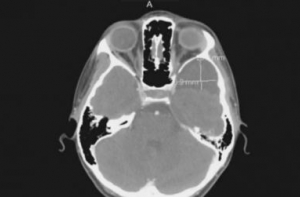

Как сообщает Business Insider, диагноз Британи Мэтис был поставлен год назад, в декабре 2012 года, но ее медстраховка не покрывает стоимости лечения и операции.